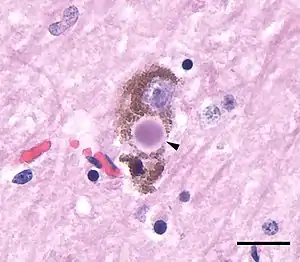

| Microscopic image of a Lewy body (arrowhead) in a neuron of the substantia nigra; scale bar=20 microns (0.02 mm) | |

Most people with DLB do not have affected family members, although occasionally DLB runs in a family. The exact cause is unknown but involves formation of abnormal clumps of protein in neurons throughout the brain. Manifesting as Lewy bodies (discovered in 1912 by Frederic Lewy) and Lewy neurites, these clumps affect both the central and the autonomic nervous systems. Heart function and every level of gastrointestinal function—from chewing to defecation—can be affected, constipation being one of the most common symptoms. Low blood pressure upon standing can also occur. DLB commonly causes psychiatric symptoms, such as altered behavior, depression, or apathy.